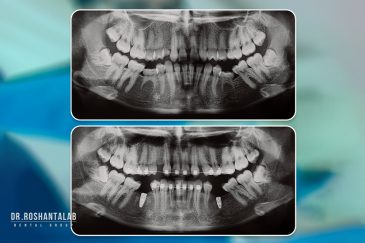

تجربه ایمپلنت دیجیتال بدون درد، سریع و ایمپلنت فوری دندان با بهره گیری از جدیدترین تکنولوژی دیجیتال در کلینیک دکتر روشنطلب؛ جایی که آرامش شما اولویت است.

🔸 کاشت دندان یک روزه ( کشیدن و کاشت همزمان )

🔸 ایمپلنت دیجیتال و ساخت روکش دیجیتال

تجربه کاشت دندان دیجیتال و بدون درد در ۳ دقیقه! استفاده از برترین برندها زیر نظر جراح، با هزینه مناسب و خدمات کامل از کاشت دندان تا روکشارتودنسی دندان

انتخاب بهترین متخصص ایمپلنت که به تکنیکهای روز دنیا مسلط باشد، تضمینکننده سلامت فک و زیبایی لبخند شماست. در کلینیک دندانپزشکی دکتر روشنطلب، ما با بهرهگیری از تجهیزات دیجیتال در ۵ شعبه فعال (تهران، اصفهان، رشت و استانبول ترکیه)، خدمات تخصصی کاشت ایمپلنت دندان را برای بیمارانی که کیفیت و دقت برایشان اولویت دارد، ارائه میدهیم. در این متد، پروسه درمان با ظرافت بالا انجام شده؛ راهکاری ایدهآل برای کسانی که به دنبال درمان بدون درد با بالاترین نرخ موفقیت هستند.